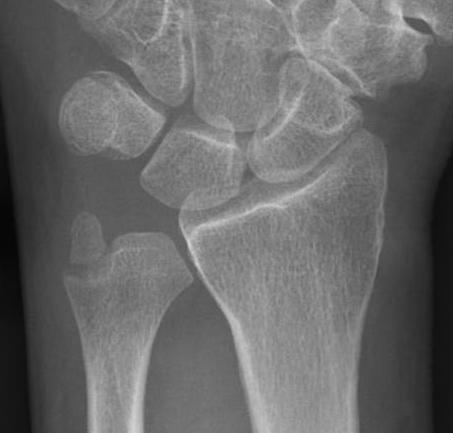

Distal radius fracture with DRUJ instability

Management

DRUJ instability after distal radius fracture ORIF

- 100 cases of DRUJ instability after distal radius ORIF

- 50 treated with arthroscopic capsular repair

- 50 treated in cast

- better outcomes with capsular repair

www.boneschool.com/distal-radius-fractures